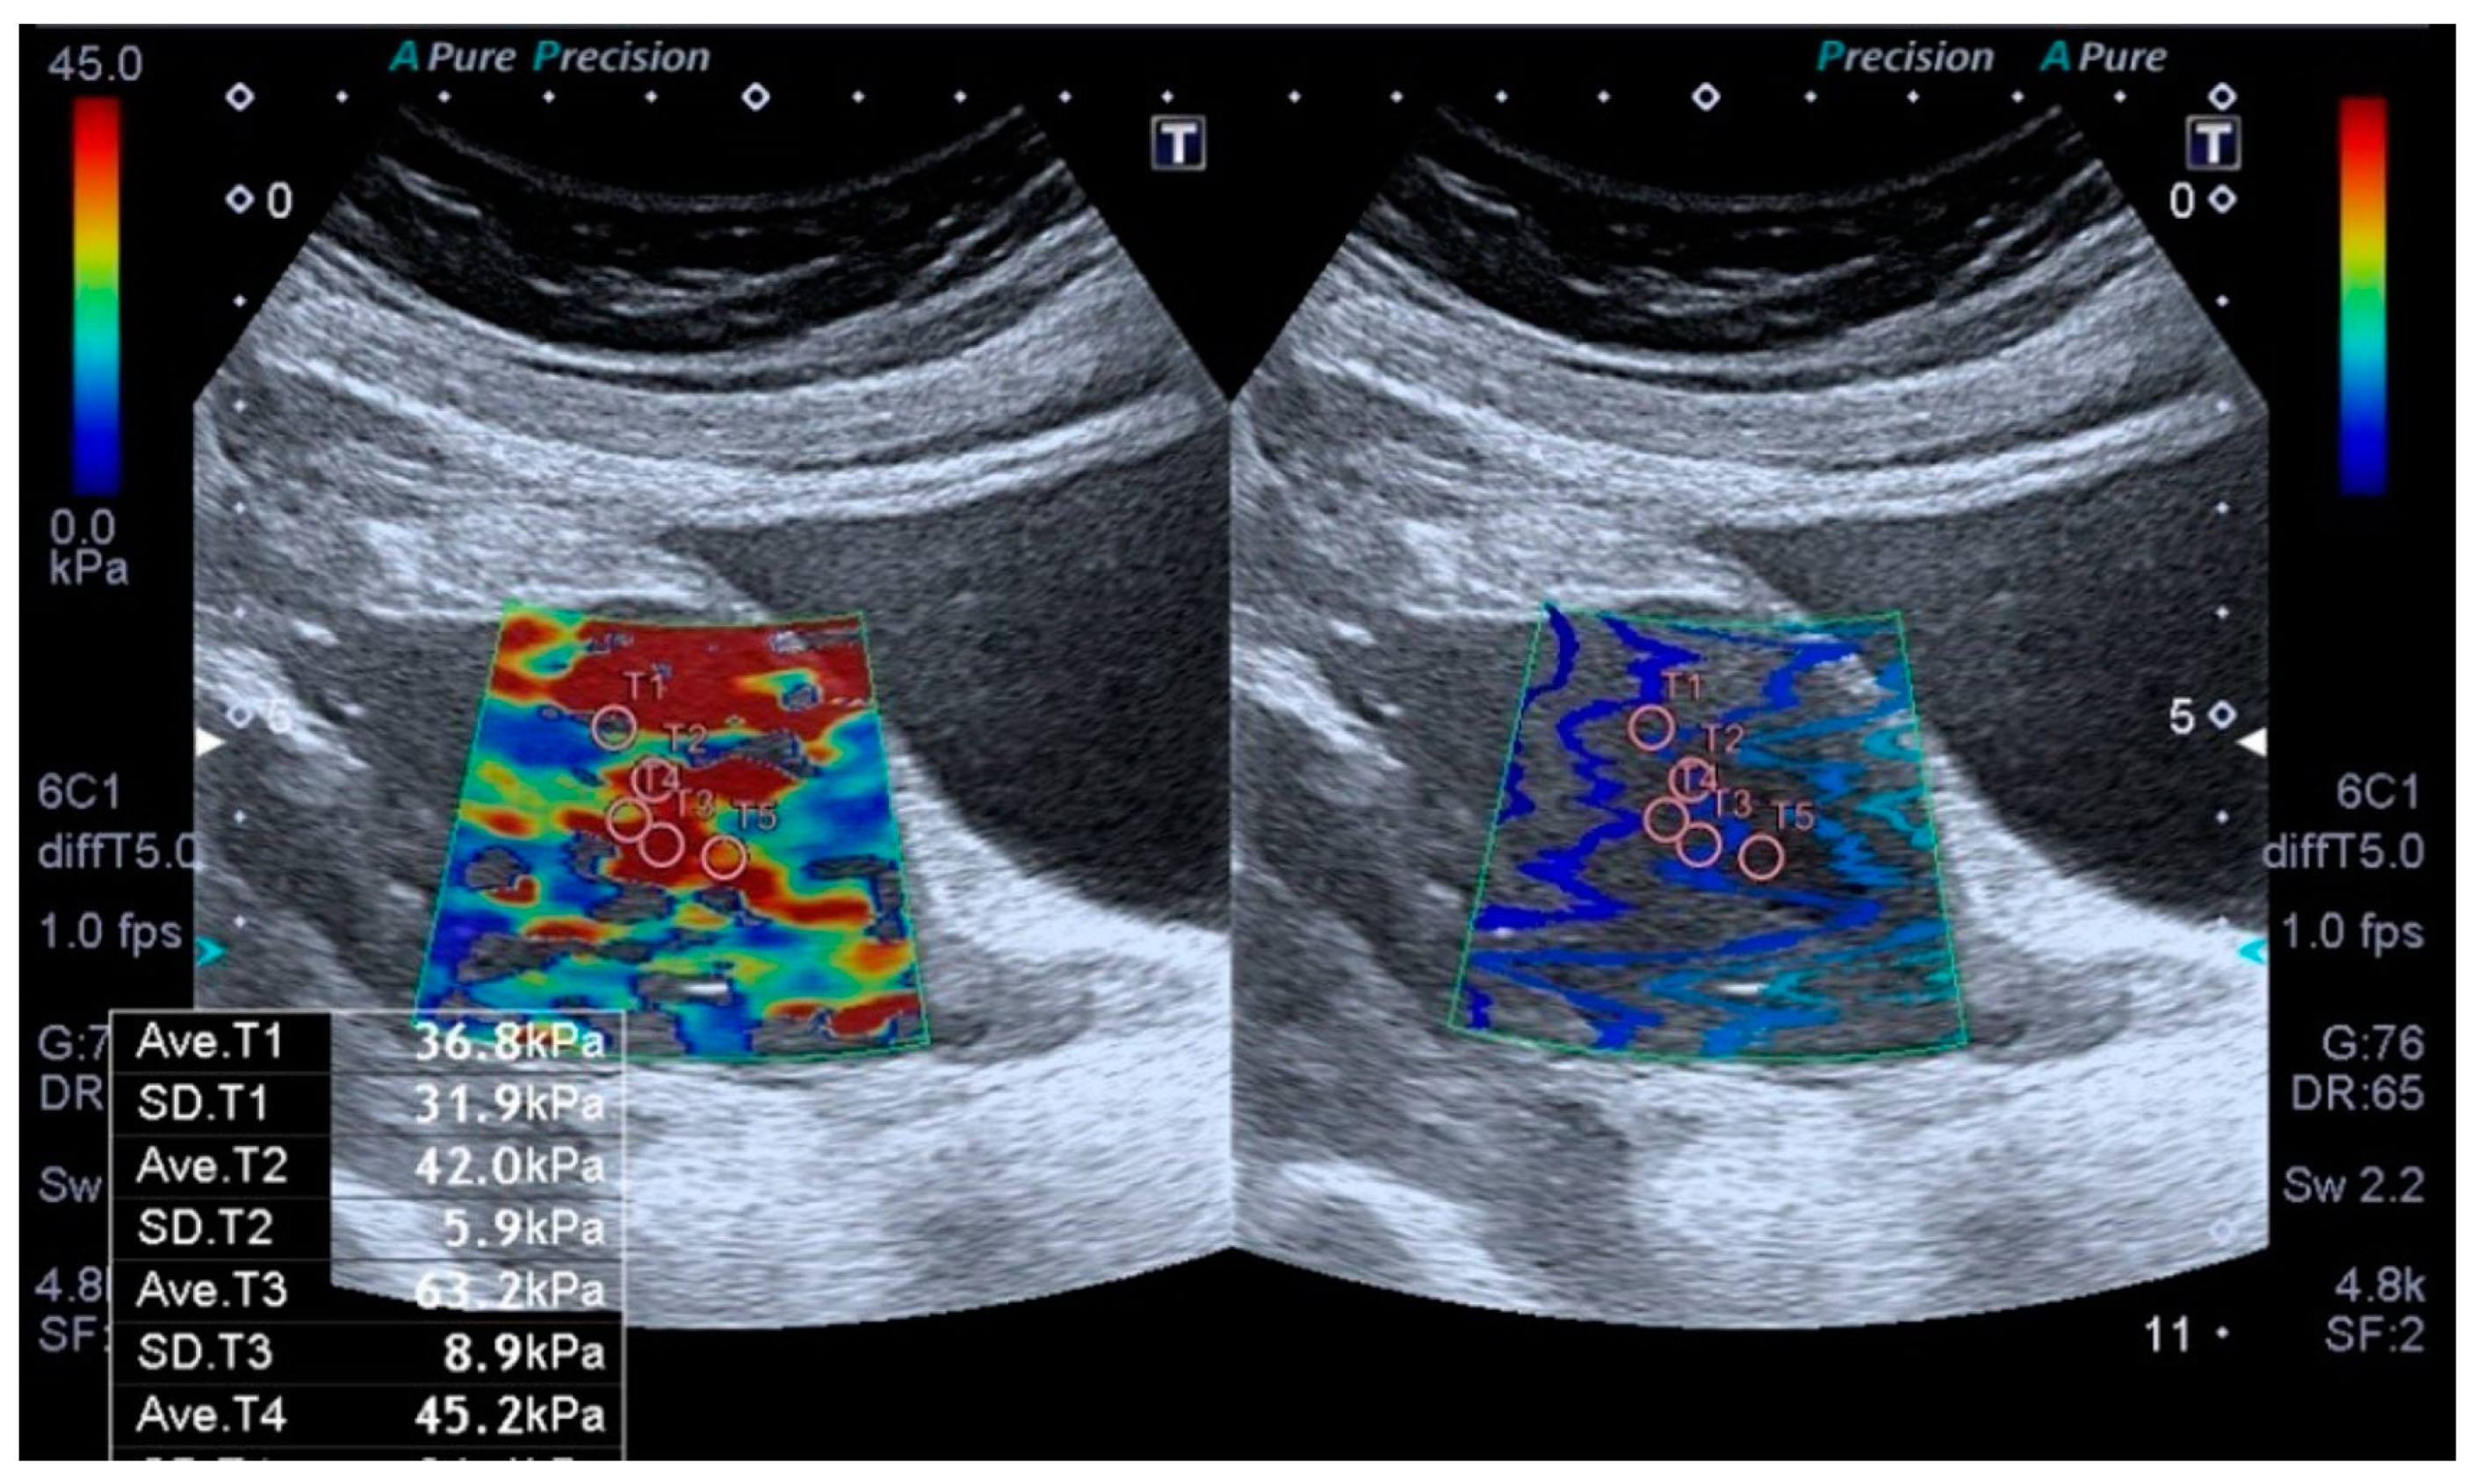

| Shear Wave Elastography (SWE. kPa) (n = 29) | Mean ± SD | Median (Min–Max) |

| kPa Measurement | 39.56 ± 14.21 | 36.5 (19.1–70.4) |

| <40 kPa n (%) | 18 (62.1%) | |

| ≥40 kPa n (%) | 11 (37.9%) | |